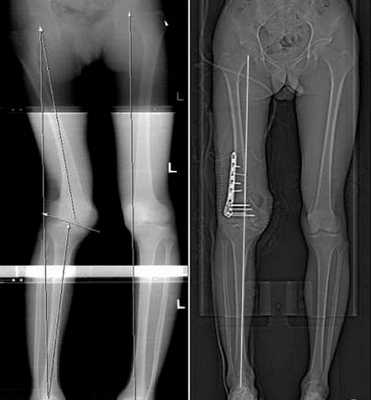

Корригирующие остеотомии (пересечение кости) с одномоментной коррекцией деформации (без удлинения) и фиксацией (при помощи ортопедических имплантов);

Коррекция деформации и удлинение конечностей методом Илизарова. Для этого выполняется остеотомия, устанавливается чрескостный аппарат. Удлинение осуществляется путем ежедневного дозированного изменения длин резьбовых стержней между кольцевыми опорами чрескостного аппарата

Мы используем кольцевые и полукольцевые чрескостные аппараты (типа Илизарова). Устранение деформации (в конце периода удлинения), в большинстве случаев, осуществляется при помощи узла на базе компьютерной навигации Орто-СУВ (гексапод).

1 цикл - параллельное удлинение и коррекция деформаций обеих голеней;

2 цикл - перекрестное удлинение и коррекция деформаций бедро- голень;

3 цикл - перекрестное удлинение и коррекция деформаций бедро-голень (противоположных).

Цикл составляет от 6 месяцев до 1 года. Между циклами - перерыв не менее1 года.Между первым и вторым циклами удлинения нижних конечностей - удлинение плеч.Повторное удлинение плеч (при необходимости) после 3-его цикла удлинения нижних конечностей.